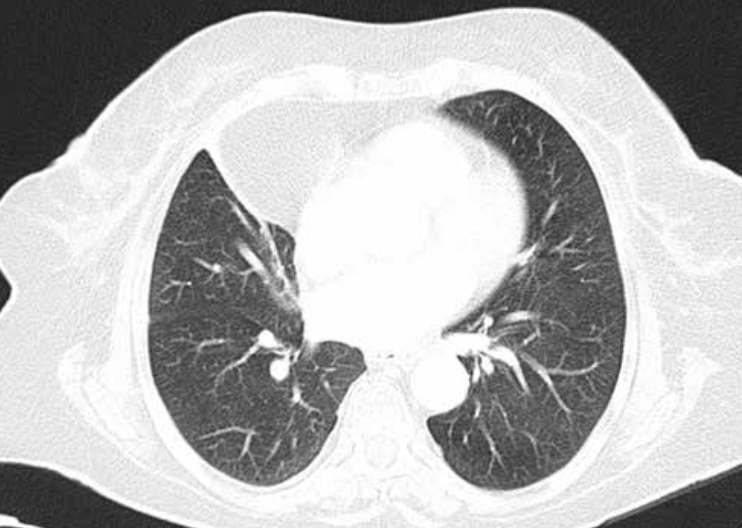

TC ventana pulmonar

Se ven mejor la vía aérea, vasos pulmonares y cisuras, pero todas las estructuras mediastínicas aparecen de un tono gris demasiado similar.